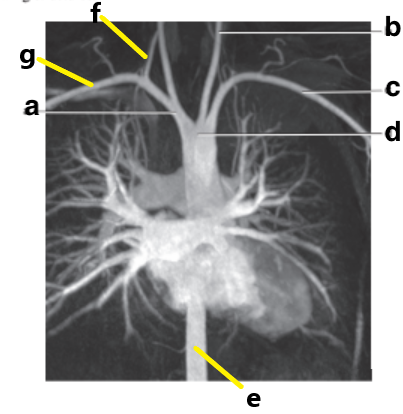

Left common carotid artery

Supplies blood to the left side of the neck and head.

Left subclavian artery

Supplies blood to the left upper extremity

Brachiocephalic trunk

Divides into the right common carotid and right subclavian arteries

Which letter is the Left common carotid ?

b

Which letter is the left subclavian artery ?

Which letter is the Right common carotid artery ?

d

What is letter a ?

Which letter is the right subclavian artery ?

g

c

a

Which letter is the brachiocephalic trunk ?